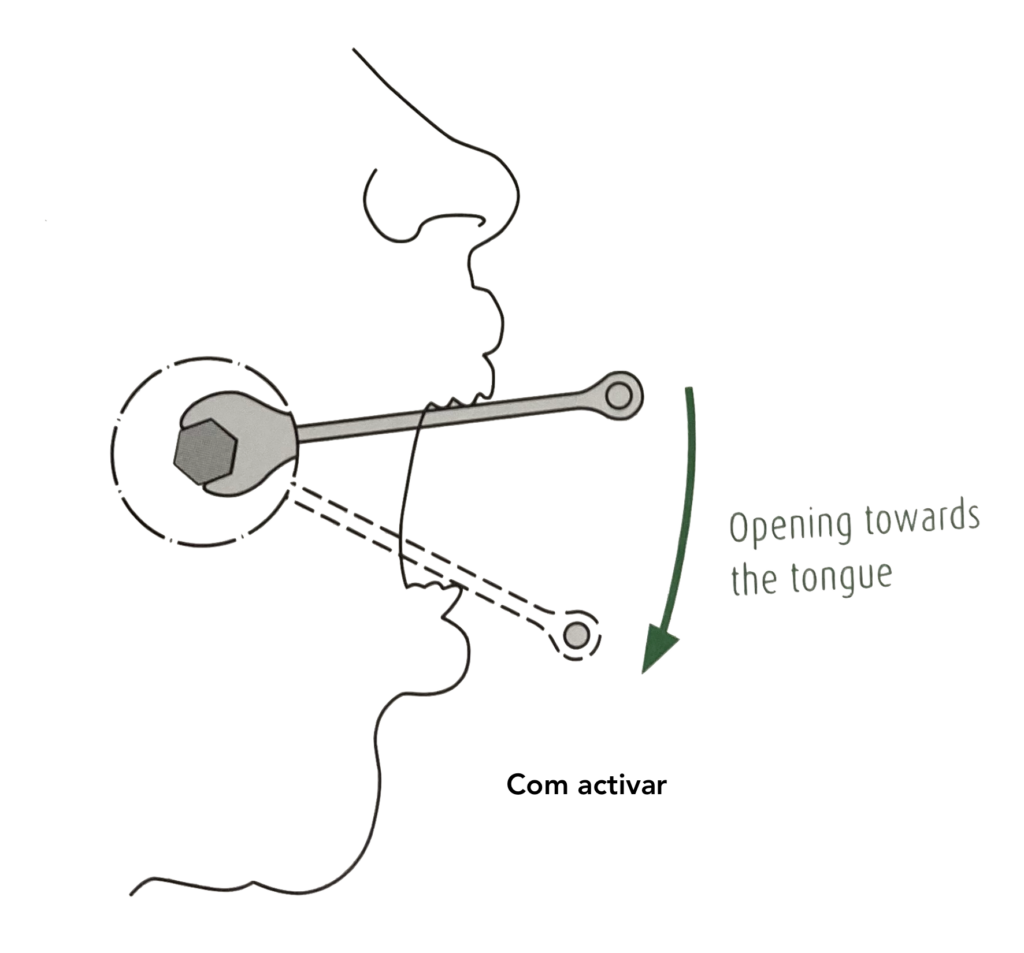

2. COM REALITZAR LES ACTIVACIONS: